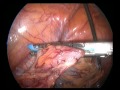

Лечение рака яичников Интервальная химиотерапия и лапароскопия